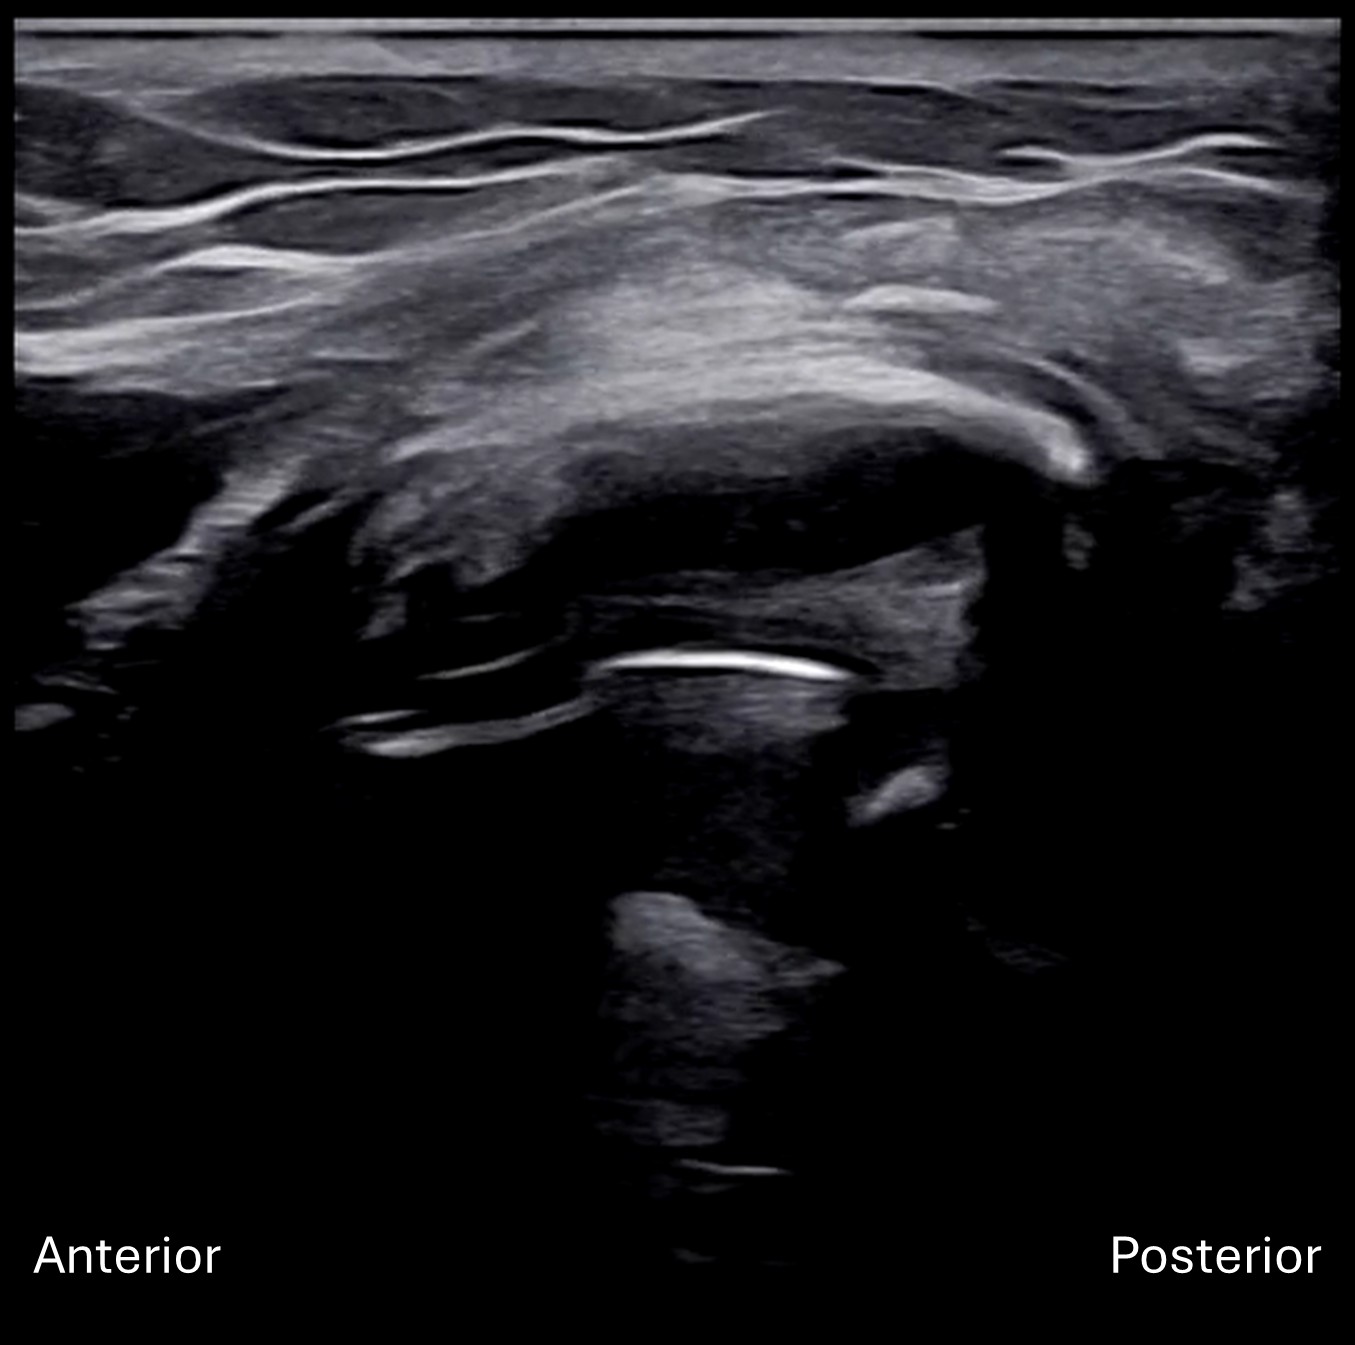

Unlabeled short axis view of the left PIN within the radial tunnel.